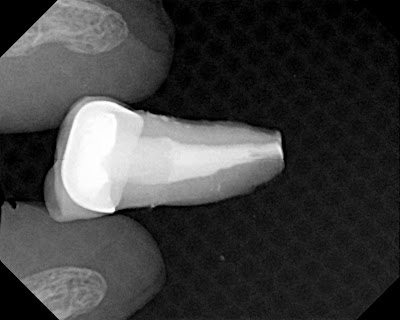

RCT was completed and patient continued to have apical pain. Extrusion of sealer was assumed to be the cause of the apical periodontitis. Close proximity to the mental foramen makes apical surgery contraindicated.

Following atraumatic extraction, the gross overextension of gutta percha is obvious. Apical resection and burnishing of gutta percha completed within minutes.

Tooth replanted and treatment completed.